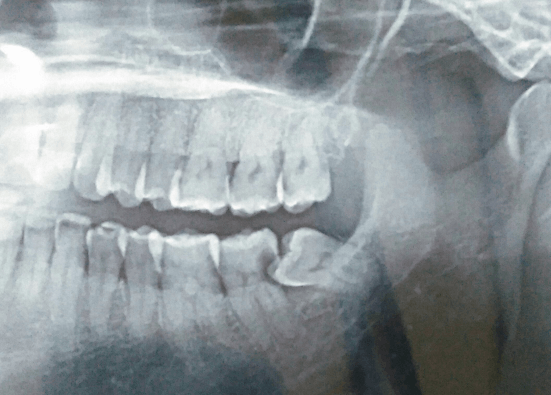

Operasi gigi merupakan prosedure medis dengan melakukan tindakan operasi kecil untuk mencabut gigi bungsu yang bermasalah dengan melakukan penyobekan terlebih dahulu pada gusi untuk memberikan ruang saat proses pencabutan gigi bungsu dilakukan. Dalam melakukan operasi ini pasien akan diberikan bius total sehingga pasien tidak sadarkan diri selama operasi berlangsung agar tidak merasakan sakit ketika operasi dilakukan.